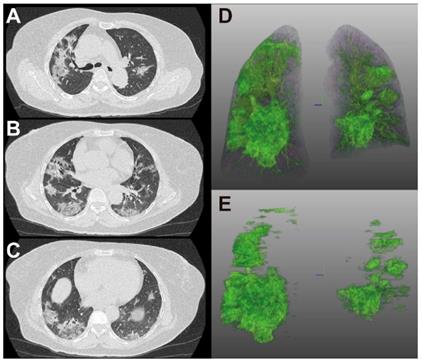

Figure 4 and 5 showed two typical cases with and without clinical endpoint during hospitalization.

Figure 5

66-year-old woman with coronavirus disease 2019. A-C. Non-contrast CT was performed on day of admission. D. Three-dimensional volume-rendered reconstruction shows the distribution of the opacities. E. Pulmonary opacities segmented by AI system. The patient showed fever and cough at admission. Patient did not reach clinical endpoint during hospitalization. Lung CT images showed that consolidation and ground-glass opacities mainly distributed in the lower lungs.

Theranostics Image